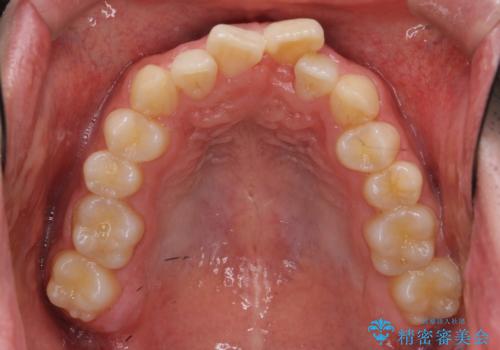

- 前歯のがたつきを主訴に来院。

左下の奥歯を後ろに移動して、中に入ってすれちがっていた小臼歯を並べました。

巷(ちまた)で大きく宣伝している某 格安マウスピース矯正では、奥歯を後ろに動かすことはできないです。

他院で歯を抜かずにマウスピースで難しいといわれた方、ぜひご相談ください。